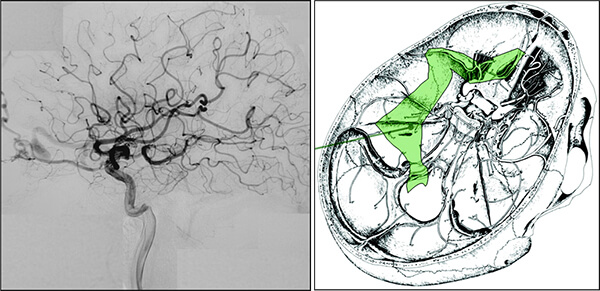

Η αξονική αγγειογραφία έχει ελαττωμένη ευαισθησία έναντι της μαγνητικής αγγειογραφίας.

Παρ´ όλα αυτά η συμβατική ενδαρτηριακή αγγειογραφία είναι η πιό ακριβής γιά την αναγνώριση αλλά και την κατηγοριοποίηση των ΑΦΔ της σκληράς μήνιγγας.

Η φλεβική προσπέλαση:

- Συνίσταται σε παλίνδρομο καθετηριασμό του φλεβώδους κόλπου ή της φλοιώδους φλέβας που αποφράσσεται με μεταλλικά σπειράματα (coils) ή υγρή κόλλα (Onyx).

- Ενδείκνυται και είναι ασφαλής όταν το πάσχον τμήμα του φλεβώδους κόλπου δεν συμμετέχει στην παροχέτευση φυσιολογικού εγκεφάλου. Χρειάζεται όμως προσοχή ώστε μα μήν εκτρέψουμε την φλεβική παροχέτευση προς τον εγκέφαλο προκαλώντας φλεβική συμφόρηση.

- Ως πιθανοί κίνδυνοι εφόσον αποφράξουμε φυσιολογική φλοιώδη παροχέτευση, να προκαλέσουμε φλεβικό έμφρακτο με αιμορραγική μετατροπή.